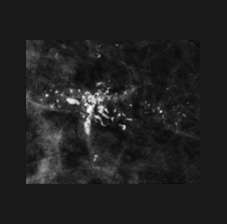

Calcifications Amorphous V2

Amorphous calcifications: calcifications that are so small and faint that their shapes are not appreciable, amorphous calcifications are considered a 4B category finding.